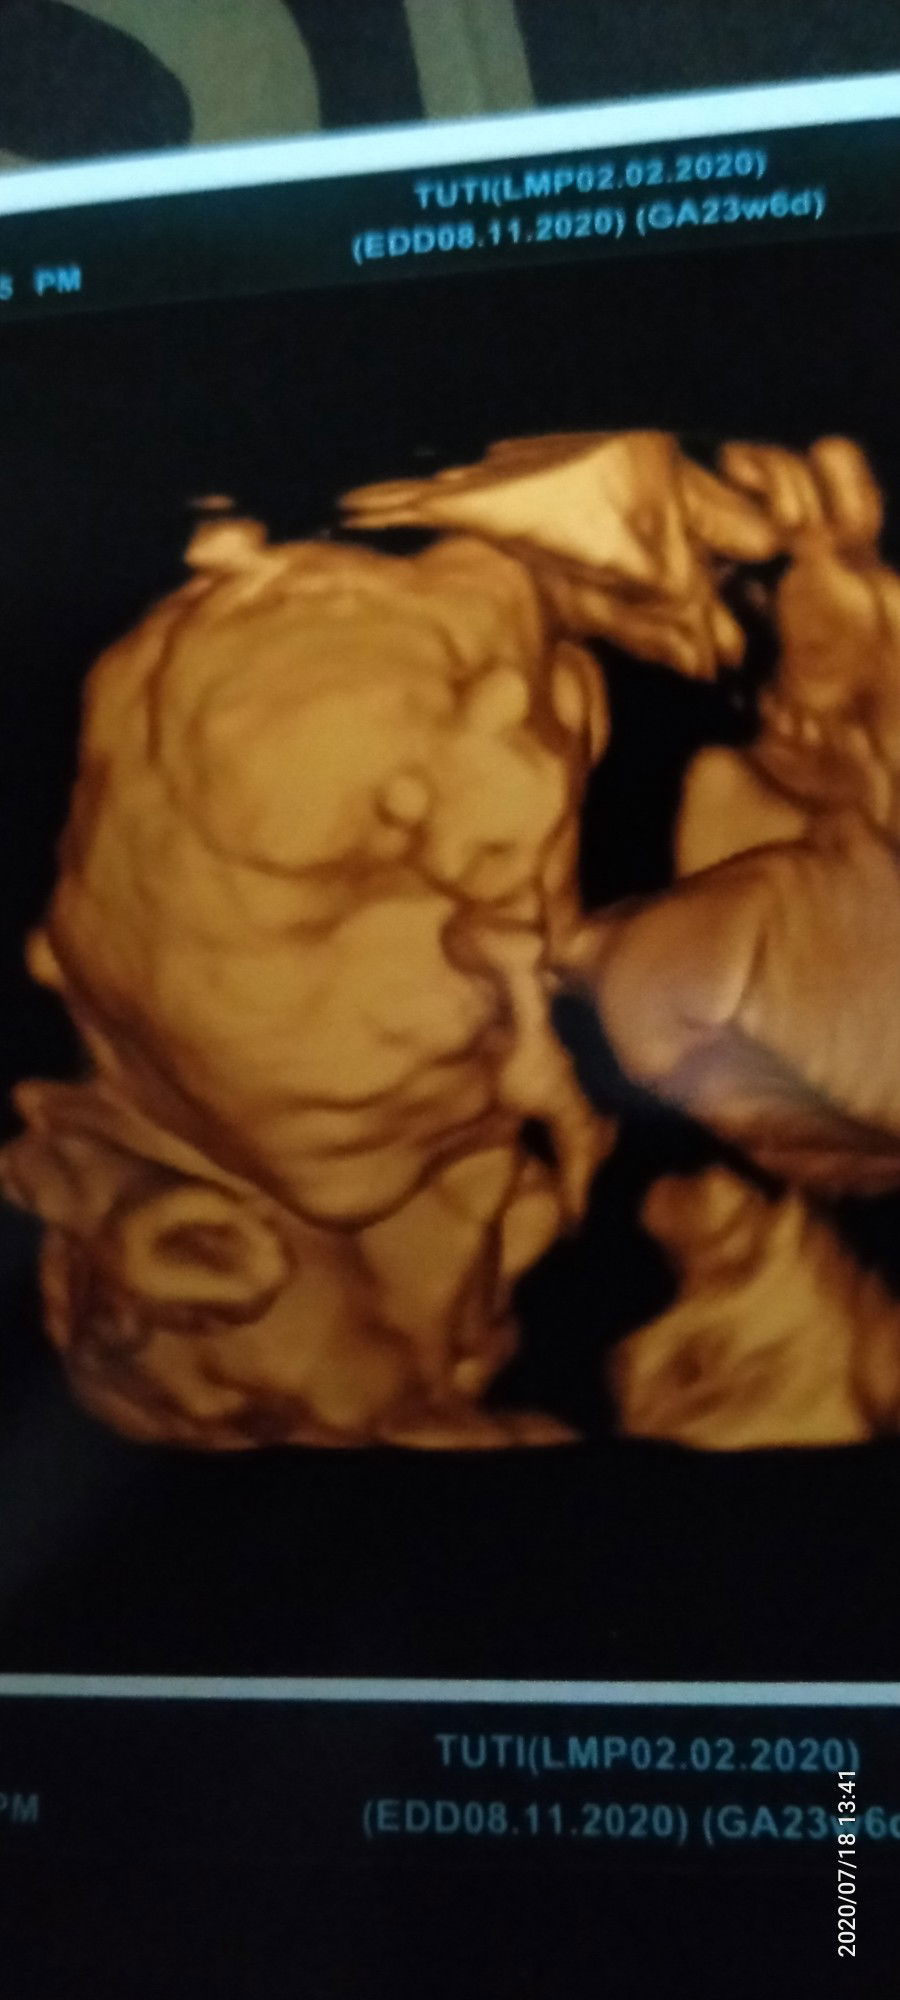

Hasil usg tadi siang hehe Alhamdulillah semua nya bagus Perkiraan baby boy Sehat sehat di perut mamah ya nak Sampai ketemu di bulan november Semoga di lancarkan segala galanya. Aamiin🥰😘 Lucu nya km malu malu nutupin muka🤗